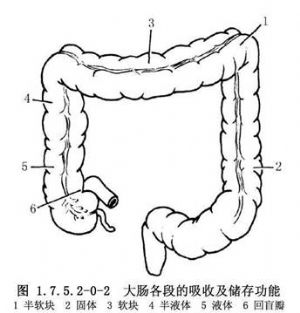

結腸長約1.5m,約爲小腸的1/4。結腸外觀上有4個特徵,易與小腸鑑別:①結腸帶:是結腸壁縱肌層集聚而成的3條縱帶,自盲腸端至乙狀結腸直腸交界處;②結腸袋:因結腸帶較短而結腸較長,引起腸壁皺縮成囊狀;③脂肪垂(腸脂垂):是結腸的髒層腹膜下脂肪組織集聚而成,沿結腸帶分佈最多,在近端結腸較扁平,在乙狀結腸則多呈帶蒂狀;④腸腔較大,腸壁較薄(圖1.7.5.2-0-1)。結腸分爲盲腸、升結腸、橫結腸及乙狀結腸等。結腸的功能主要是吸收水分和儲存糞便(圖1.7.5.2-0-2)。吸收作用以右半結腸爲主,因其內容物爲液體、半液體及軟塊樣,故主要吸收水分、無機鹽、氣體、少量的糖和其他水溶性物質,但不能吸收蛋白質與脂肪。若右半結腸蠕動降低,則加強吸收能力;橫結腸內若有硬的糞塊,常導致便祕。左半結腸的內容物爲軟塊、半軟塊或固體樣,故僅能吸收少量的水分、鹽和糖。若左半結腸腸蠕動增強,則降低吸收能力,常有腹瀉或稀便。結腸黏膜僅能分泌黏液,使黏膜潤滑,以利糞便通過。切除結腸後,吸收水分的功能逐漸由迴腸所代替,故主要對切除結腸的任何部分,甚至全部,也不致造成永久性代謝障礙。